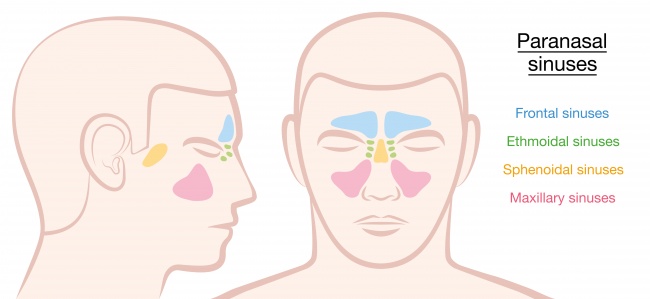

2. 鼻竇。

沒人知道我們為何有這些會分泌黏液的氣腔。